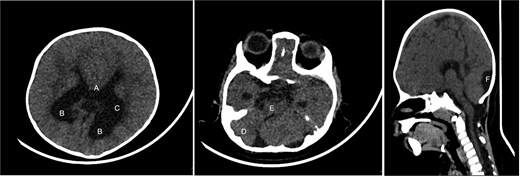

An 11-month-old female infant, born to unrelated Saudi parents, was referred to our facility with unilateral left coronal craniosynostosis, congenital microcephaly, global developmental delay, and a confirmed ZIC1 gene mutation. Comorbidities included a patent foramen ovale, aortopulmonary collateral vessel, G6PD deficiency, and gastroesophageal reflux disease (GERD). At birth head circumference was 29 cm (<first percentile), and progressive skull asymmetry and squinting were noted over time. Developmentally, she exhibited delayed gross and fine motor skills with limited object transfer. On examination, she was alert and visually tracking, with inward ocular deviation (esotropia). Head circumference was 37 cm (<first percentile) with anterior plagiocephaly and towering of the left frontal region (Fig. 1). Pupils were equal and reactive. Fundoscopy and cranial nerve examinations were unremarkable. Gross motor power was within normal limits, except for moderate lower limb spasticity. 3D reconstruction computed tomography (CT) confirmed premature fusion of the left coronal suture with subtle elevation of the superolateral orbital rim, indicating harlequin sign (Fig. 1). Brain CT showed corpus callosum agenesis, colpocephaly, mild ventriculomegaly, right cerebellar and pontine hypoplasia, and a large cisterna magna, consistent with the reported ZIC1-related malformation spectrum (Fig. 2). Given the progressive deformity and concerns of increased intracranial pressure that might be partially contributing to her neurodevelopmental delay, anterior cranial vault expansion with fronto-orbital advancement was performed jointly by the neurosurgery and plastic craniofacial teams (Fig. 3). Intraoperatively, left-sided dural tension was appreciated, indicating localized increased intracranial pressure. The orbital bandeau was reshaped and advanced, achieving immediate cosmetic improvement (Fig. 4). The patient tolerated the surgery well and recovered uneventfully. At her 4-month follow-up, she showed developmental progress including standing without support, purposeful hand use, and verbalization (“Baba”). At 6-month follow-up, brain CT revealed areas of bone resorption which led to the placement of a ventriculo-peritoneal shunt (Fig. 5). The known association of ZIC1 mutation with tethering of the cord prompted spinal magnetic resonance imaging (MRI) screening. Positive findings indicated an untethering procedure, which was successfully done (Fig. 6).

Brain CT showing: A-corpus callosum agenesis, B-colpocephaly, C-mild ventriculomegaly, D-right cerebellar and E-pontine hypoplasia, F-large cisterna magna.